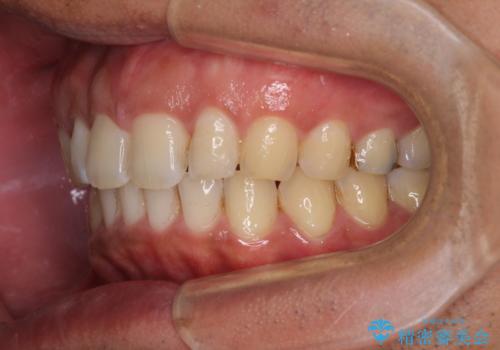

- 上顎前歯の突出感とすきっ歯を気にして来院された患者様です。

奥歯の咬み合わせを見ると、下顎に対して上顎が前方に位置していたため、補助装置により上顎歯列全体を後方に移動させ、その後インビザラインにて歯列全体を整えることとしました。